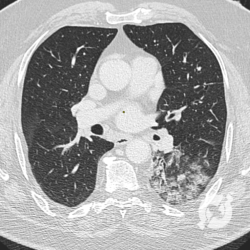

Os agentes etiológicos infecciosos são variados (bactérias, vírus, fungos, parasitas…), mas o que ocorre nos pulmões durante uma infecção por qualquer tipo de agente é a substituição do ar alveolar por secreção (pus, muco, eventualmente sangue ou necrose…) e com isso a manifestação radiográfica vai ser a mesma já que todas estas secreções apresentam a mesma densidade radiográfica: partes moles.

E o nome dado a esta alteração radiográfica que corresponde à substituição do ar alveolar por líquido é a consolidação alveolar.

Uma consolidação alveolar é, por definição, uma opacidade (imagem densa, branquinha) homogênea ou às vezes heterogênea (pela presença de calcificações ou cavidades), de limites mal definidos, exceto quando toca a pleura da parede ou das cissuras pulmonares. É um termo usado tanto em radiografia, como em tomografia computadorizada. Na tomografia, um outro termo é usado: vidro fosco, que é uma opacidade (branquinha mas não tanto como a consolidação), que borra o pulmão mas deixa ver os vasos de permeio (igual bigode de adolescente: dá pra ver todo o fundo).

Nós vamos mostrar aqui um pequeno apanhado de pneumonias de variados agentes, em diversos segmentos e lobos pulmonares, com extensões variadas. O objetivo é identificar o padrão radiológico de consolidação alveolar e não determinar o agente infeccioso, isso vai ser assunto para mais adiante. Aliás já antecipo que é fundamental saber localizar a lesão, porque alguns destes bichos gostam de determinados segmentos, alguns tumores também têm as suas preferências, então localização é fundamental. Se localização não fosse importante, um apartamento na beira do mar sairia o mesmo preço de um apartamento de frente pra BR-101, concordam?